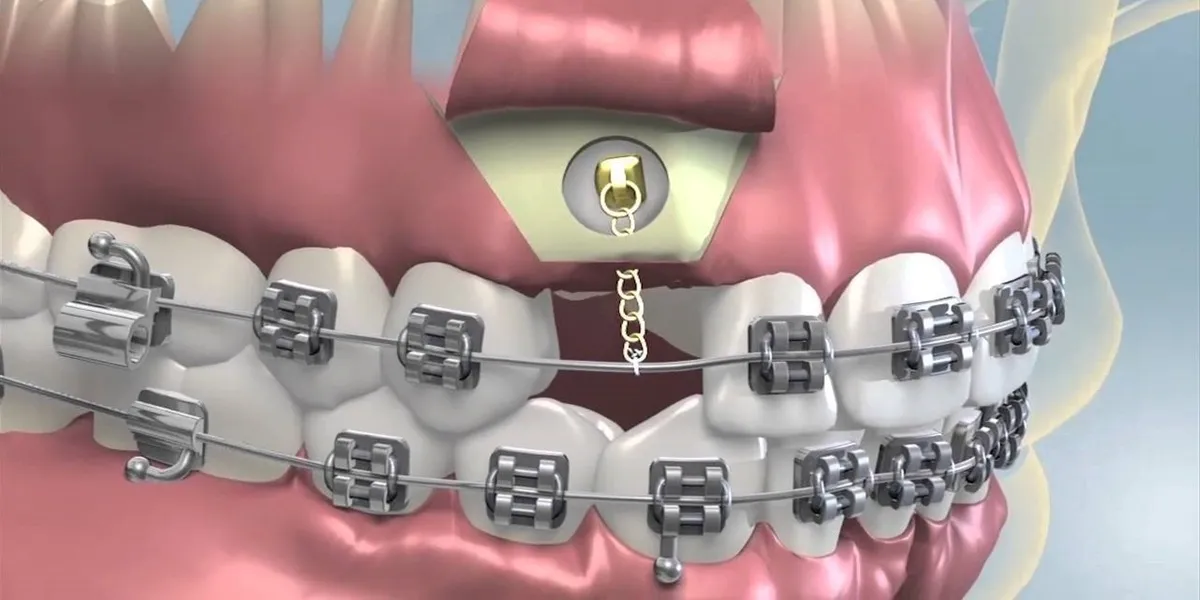

امروزه ارتودنسی دیگر تنها محدود به براکتهای فلزی سنتی نیست. با پیشرفت فناوریهای دندانپزشکی و ابزارهای نوین، روشهای جدید ارتودنسی دندان امکان اصلاح ناهنجاریهای دندانی و فکی را بدون درد و با زیبایی بیشتر فراهم کردهاند. این روشها، ضمن کاهش زمان درمان و افزایش راحتی بیمار، زیبایی لبخند را به…